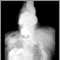

Hiatal hernia - X-ray

A hiatal hernia occurs when the natural opening in your diaphragm is too large. Your diaphragm is the muscle and tissue layer between your chest and belly. Your stomach may bulge through this large hole into your chest. This bulging is called a hiatal hernia. It may make GERD symptoms worse.